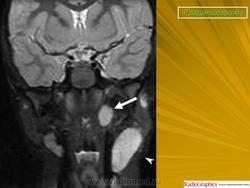

Рабдомиосаркома — чрезвычайно агрессивная опухоль орбиты, является наиболее частой причиной злокачественного роста в орбите у детей. Мальчики болеют почти в 2 раза чаще. Источником роста рабдомиосаркомы являются клетки скелетных мышц. Выделены три типа опухоли: эмбриональный, альвеолярный и плеоморфный, или дифференцированный. Последний тип встречается редко. У детей до 5 лет чаще развивается эмбриональный тип опухоли, после 5 лет — альвеолярный. Как правило, рабдомиосаркома состоит из элементов нескольких типов (смешанный вариант). Точный диагноз можно установить только на основании результатов электронной микроскопии.

Излюбленная локализация опухоли — верхневнутренний квадрант орбиты, поэтому в процесс рано вовлекаются мышца, поднимающая верхнее веко, и верхняя прямая мышца. Птоз, ограничение движений глаза, смещение его книзу и книзу кнутри — это первые признаки, на которые обращают внимание как сами больные, так и окружающие лица. У детей экзофтальм или смещение глаза при локализации опухоли в переднем отделе орбиты развивается в течение нескольких недель (рис. 20.23, а). У взрослых опухоль растет медленнее, в течение нескольких месяцев. Быстрое увеличение экзофтальма сопровождается появлением застойных изменений в эписклеральных венах, глазная щель полностью не смыкается, отмечаются инфильтраты на роговице и ее изъязвление. На глазном дне — застойный диск зрительного нерва. Первично развиваясь вблизи верхневнутренней стенки орбиты, опухоль быстро разрушает прилежащую тонкую костную стенку, прорастает в полость носа, вызывая носовые кровотечения. Ультразвуковое сканирование, компьютерная томография, термография и тонкоигольная аспирационная биопсия — это оптимальный диагностический комплекс инструментальных методов исследования при рабдомиосаркоме (рис. 20.23, б). Лечение комбинированное. Протокол лечения предусматривает предварительное проведение полихимиотерапии в течение 2 нед, после чего проводят наружное облучение орбиты. После комбинированного лечения более 3 лет живут 71 % больных.